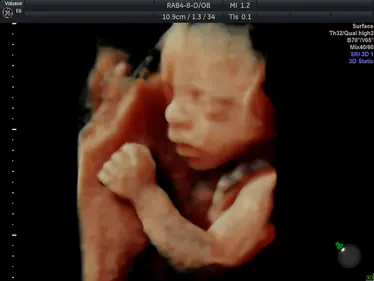

Gallery: 4D Scan Images & Videos

All of the baby scans we perform here at First Encounters are carried out using top-quality ultrasound equipment. For 3D/4D scans, we use the GE Voluson E6, featuring genuine HDLive technology. GE Healthcare are the world’s leading providers of pregnancy scanning equipment, and HD Live scans give an unparalleled level of detail and clarity.

Scroll down to view some examples of the 4D scan images and videos our sonographers are able to capture.

4D Scan Images

During your 3D/4D scan, we’ll capture multiple photographs of your unborn baby, giving you and your family a set of stunning keepsakes that you’ll treasure forever. All of your scan images will be available to download from photocloud™, plus we can provide glossy souvenir photos for you to take home.